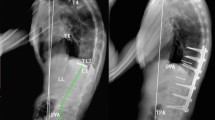

All patients were analyzed radiographically using long-cassette standing posteroanterior and lateral radiographs before operation, 2 weeks after surgery and at the latest follow-up. Radiographical analyses included T5–T12 kyphosis (TK), L1–S1 lordosis (LL), GK, osteotomized vertebral angle (OVA, for PSO, OVA was defined as the angle formed by the superior and inferior endplates of the osteotomized vertebrae; for SPO, OVA was defined as the angle between the superior endplate of the upper vertebra and the inferior endplate of the lower vertebra at the osteotomy level), pelvic tilt (PT), pelvic incidence (PI), sacral slope (SS) and sagittal vertical axis (SVA) (Fig. 1). For sagittal parameters, positive values mean kyphosis. Value of the SVA is negative if the C7 plumb line is posterior to the posterosuperior corner of S1. The corrections of these parameters were calculated by subtracting the magnitude of early postoperative (2 weeks after surgery) measurement from the magnitude of preoperative measurement. Correction loss was defined as last follow-up measurement minus the postoperative measurement.

A 32-year-old male AS patient with severe thoracolumbar kyphosis underwent L1 PSO and L3/L4 SPO. (A1,A2). The preoperative radiograph showed: GK = 97°, LL = 26°, SVA = 26.3 cm, SS = 7°, PSO-OVA = 11°, SPO-OVA = 7°. B1,B2 Postoperatively, the PSO-OVA and SPO-OVA were corrected to − 21° and − 29°, respectively. The correction of GK was 74°. The LL, SVA and SS were improved to − 49°, 4.5 cm and 22°, respectively.